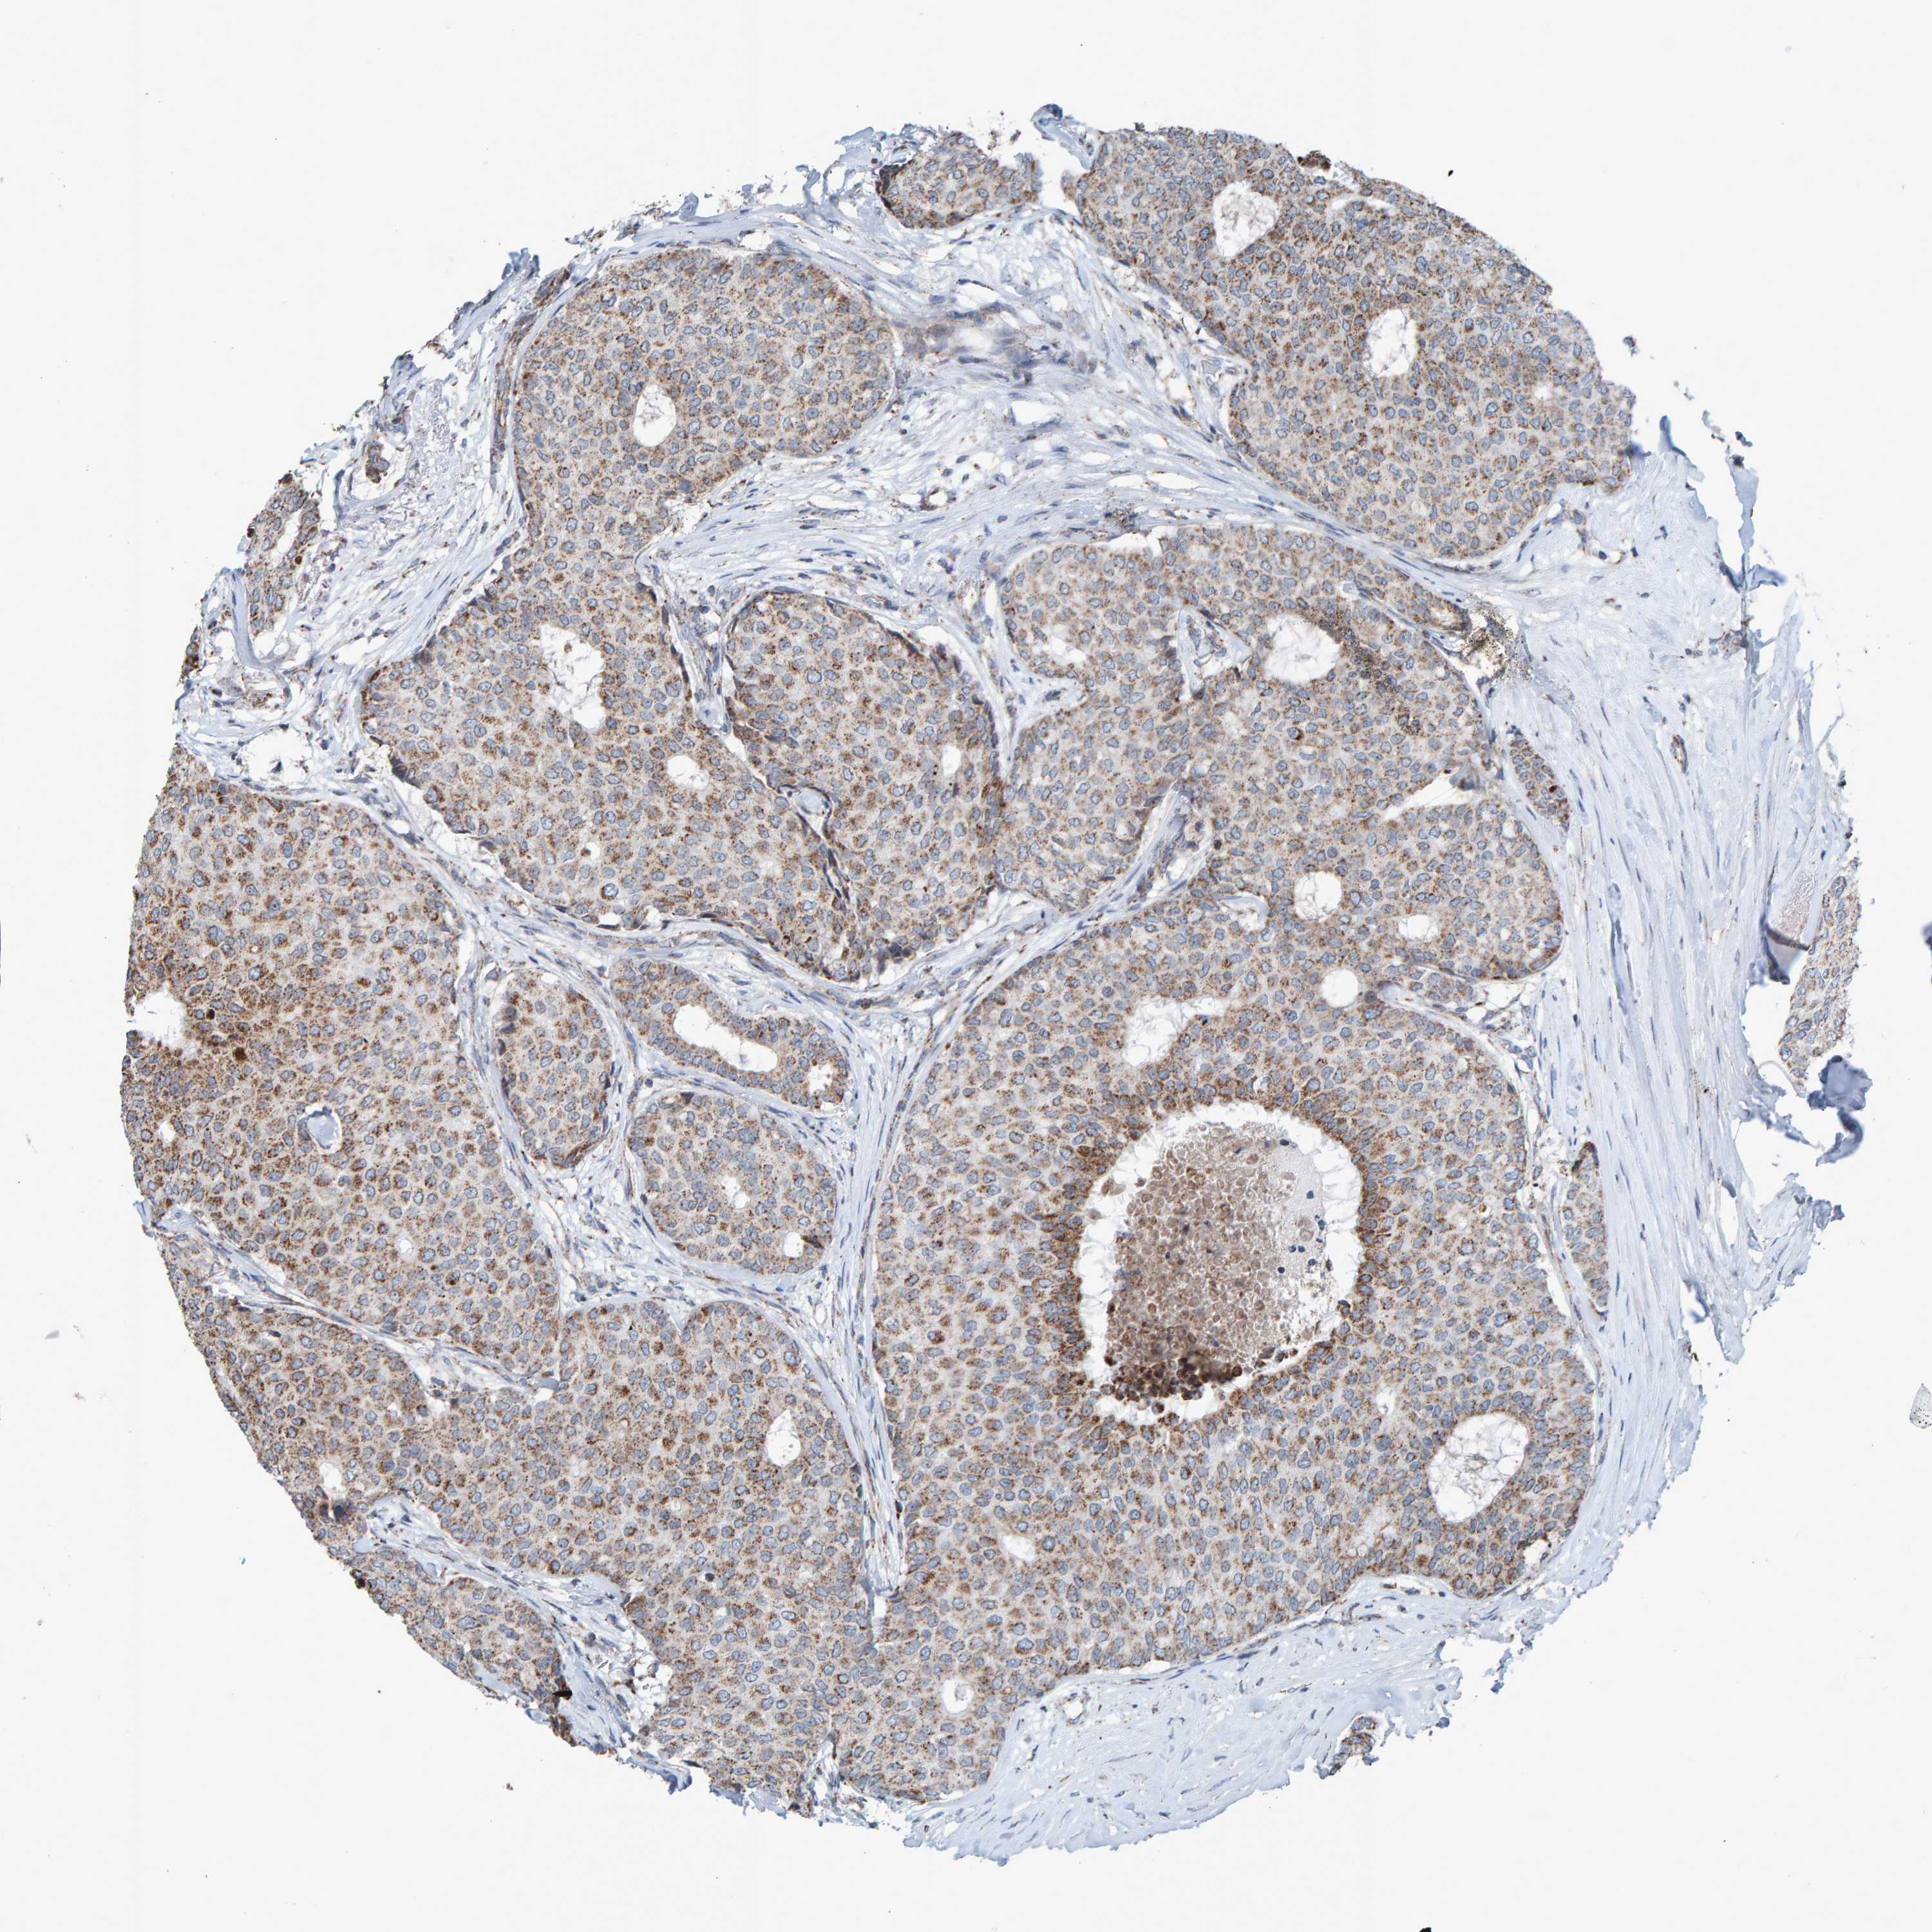

CANCER BREAST CANCER Show tissue menu

BRCA TCGA BRCA VALIDATION PROTEIN EXPRESSION

Breast cancer

Human cancer